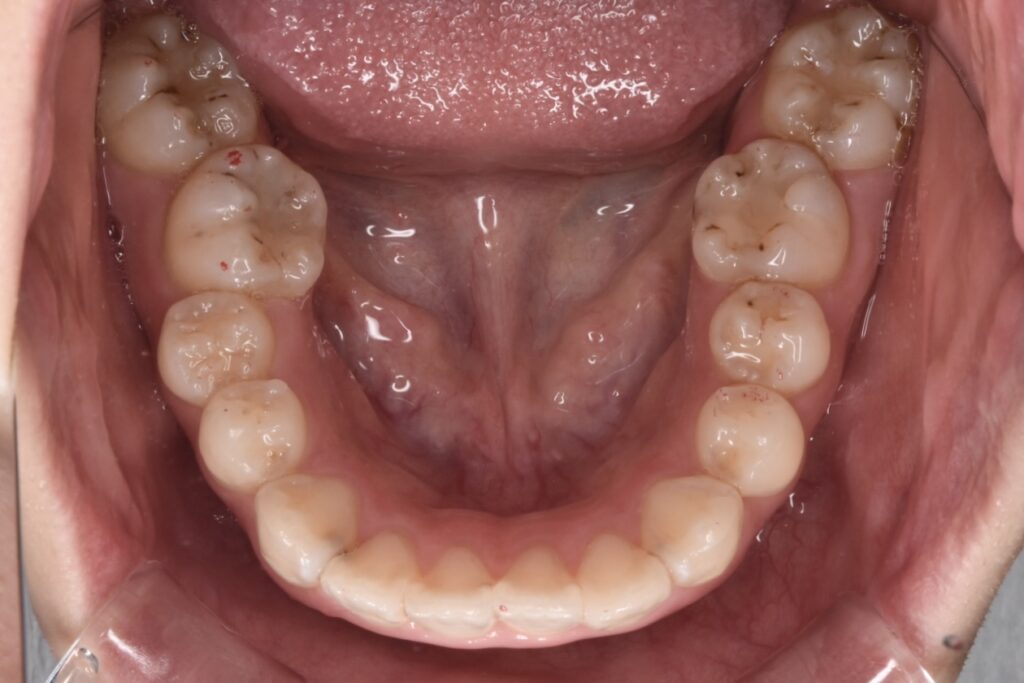

矯正前

前歯の突出感と下の歯の叢生が目立ちます。